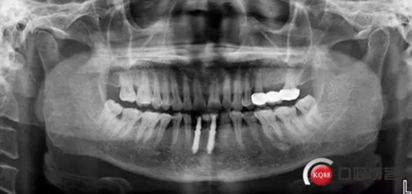

下圖是術后照片 治療過程 術前測量上下牙長度比例,確定水激光冠延長深度約3mm,拔除31、41,在術區(qū)減低牙槽嵴高度,32、42位點種植MINI型一段式種植體,使用臨時愈合帽行暫時性修復。

治療前后照片顯示患者上下臨床牙冠比例協(xié)調(diào),患者對臨時修復體效果十分滿意。當然有待后期愈合及長期的臨床隨訪,以觀察遠期臨床效果。將水激光應用臨床冠延長,有利于精準去除骨量,利于術后愈合。而MINI型一段式種植體滿足骨寬度不足,及臨時修復打下堅實基礎。